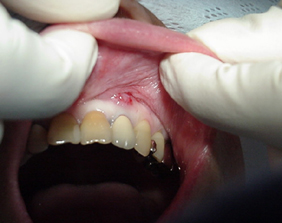

口唇粘液のう胞

唾液のような内容物をともなう膿のふくろです。麻酔をして摘出します。

くちびるが隆起しているので間違って咬んだりすることがあります。